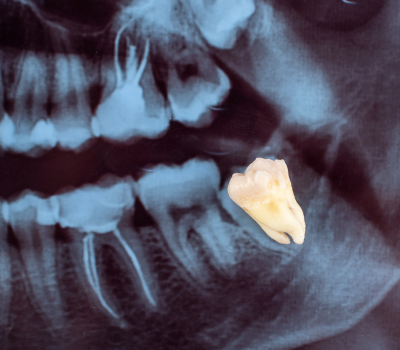

Wisdom teeth, also known as third molars, are the last set of teeth to emerge, typically between the ages of 17 and 25. While some individuals have no issues with their wisdom teeth, many experience complications due to lack of space, improper alignment, or impaction. When these teeth grow at the wrong angle or remain trapped beneath the gums, they can lead to severe pain, swelling, infection, and even damage to surrounding teeth. At Gentle Dental Clinic, we specialize in safe and minimally invasive wisdom tooth extraction, ensuring a smooth, pain-free experience that protects long-term oral health. Whether your wisdom teeth are causing discomfort now or have the potential to create problems in the future, our expert dental team provides personalized care and advanced surgical techniques to ensure a quick recovery and long-lasting results.

Not all wisdom teeth require removal, but when they cause issues, prompt extraction is the best way to prevent ongoing pain and complications. Common signs that indicate the need for removal include persistent jaw pain, swelling in the gums, difficulty opening the mouth fully, frequent infections, or pressure against adjacent teeth. In some cases, wisdom teeth can contribute to crowding, shifting of other teeth, or cyst formation, which can compromise the health of the jawbone. Our dental specialists at Gentle Dental Clinic carefully assess X-rays and oral examinations to determine whether extraction is necessary. By addressing these issues early, we help patients avoid future discomfort and expensive restorative treatments.

At Gentle Dental Clinic, we prioritize patient comfort and advanced surgical precision to make the wisdom tooth extraction process as stress-free as possible. The procedure begins with a detailed consultation and imaging scans to evaluate the position of the wisdom teeth and identify any risks. On the day of the extraction, we use local anesthesia or sedation options to ensure a completely painless experience. If the wisdom tooth is impacted, our skilled surgeons carefully remove small sections of bone or gum tissue to access the tooth without unnecessary trauma. Our advanced techniques help minimize bleeding, reduce swelling, and promote faster healing, allowing patients to recover comfortably. With our expert approach and state-of-the-art tools, we ensure that every extraction is efficient, precise, and safe.

Wisdom teeth may need extraction if they cause pain, swelling, infections, or pressure on surrounding teeth. If they are impacted, misaligned, or difficult to clean, removal is often recommended to prevent future complications. A dental exam and X-ray can help determine if extraction is necessary.